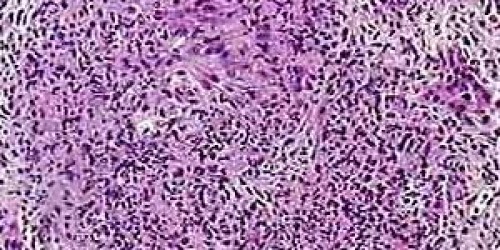

Yesterday my aunt called me and told me that my cousin maybe has wegener's granulomatosis. I was very surprised. I heard about this illness but I’ve never known anybody who had it. I know that it is very dangerous illness and I’m worried a lot. Can somebody tell me, please, what is the cause of wegener's granulomatosis?

As I know, nobody knows what the reason is why somebody can get Wegener's granulomatosis. This illness acts like an infection, but no one has found an infectious agent that causes the disease. It may involve an overactive immune system response to an allergic reaction. No one knows for sure.